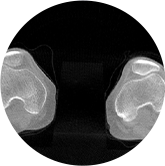

膝關(guān)節(jié)

精準(zhǔn)診斷

手術(shù)方案規(guī)劃

術(shù)后隨訪(fǎng)